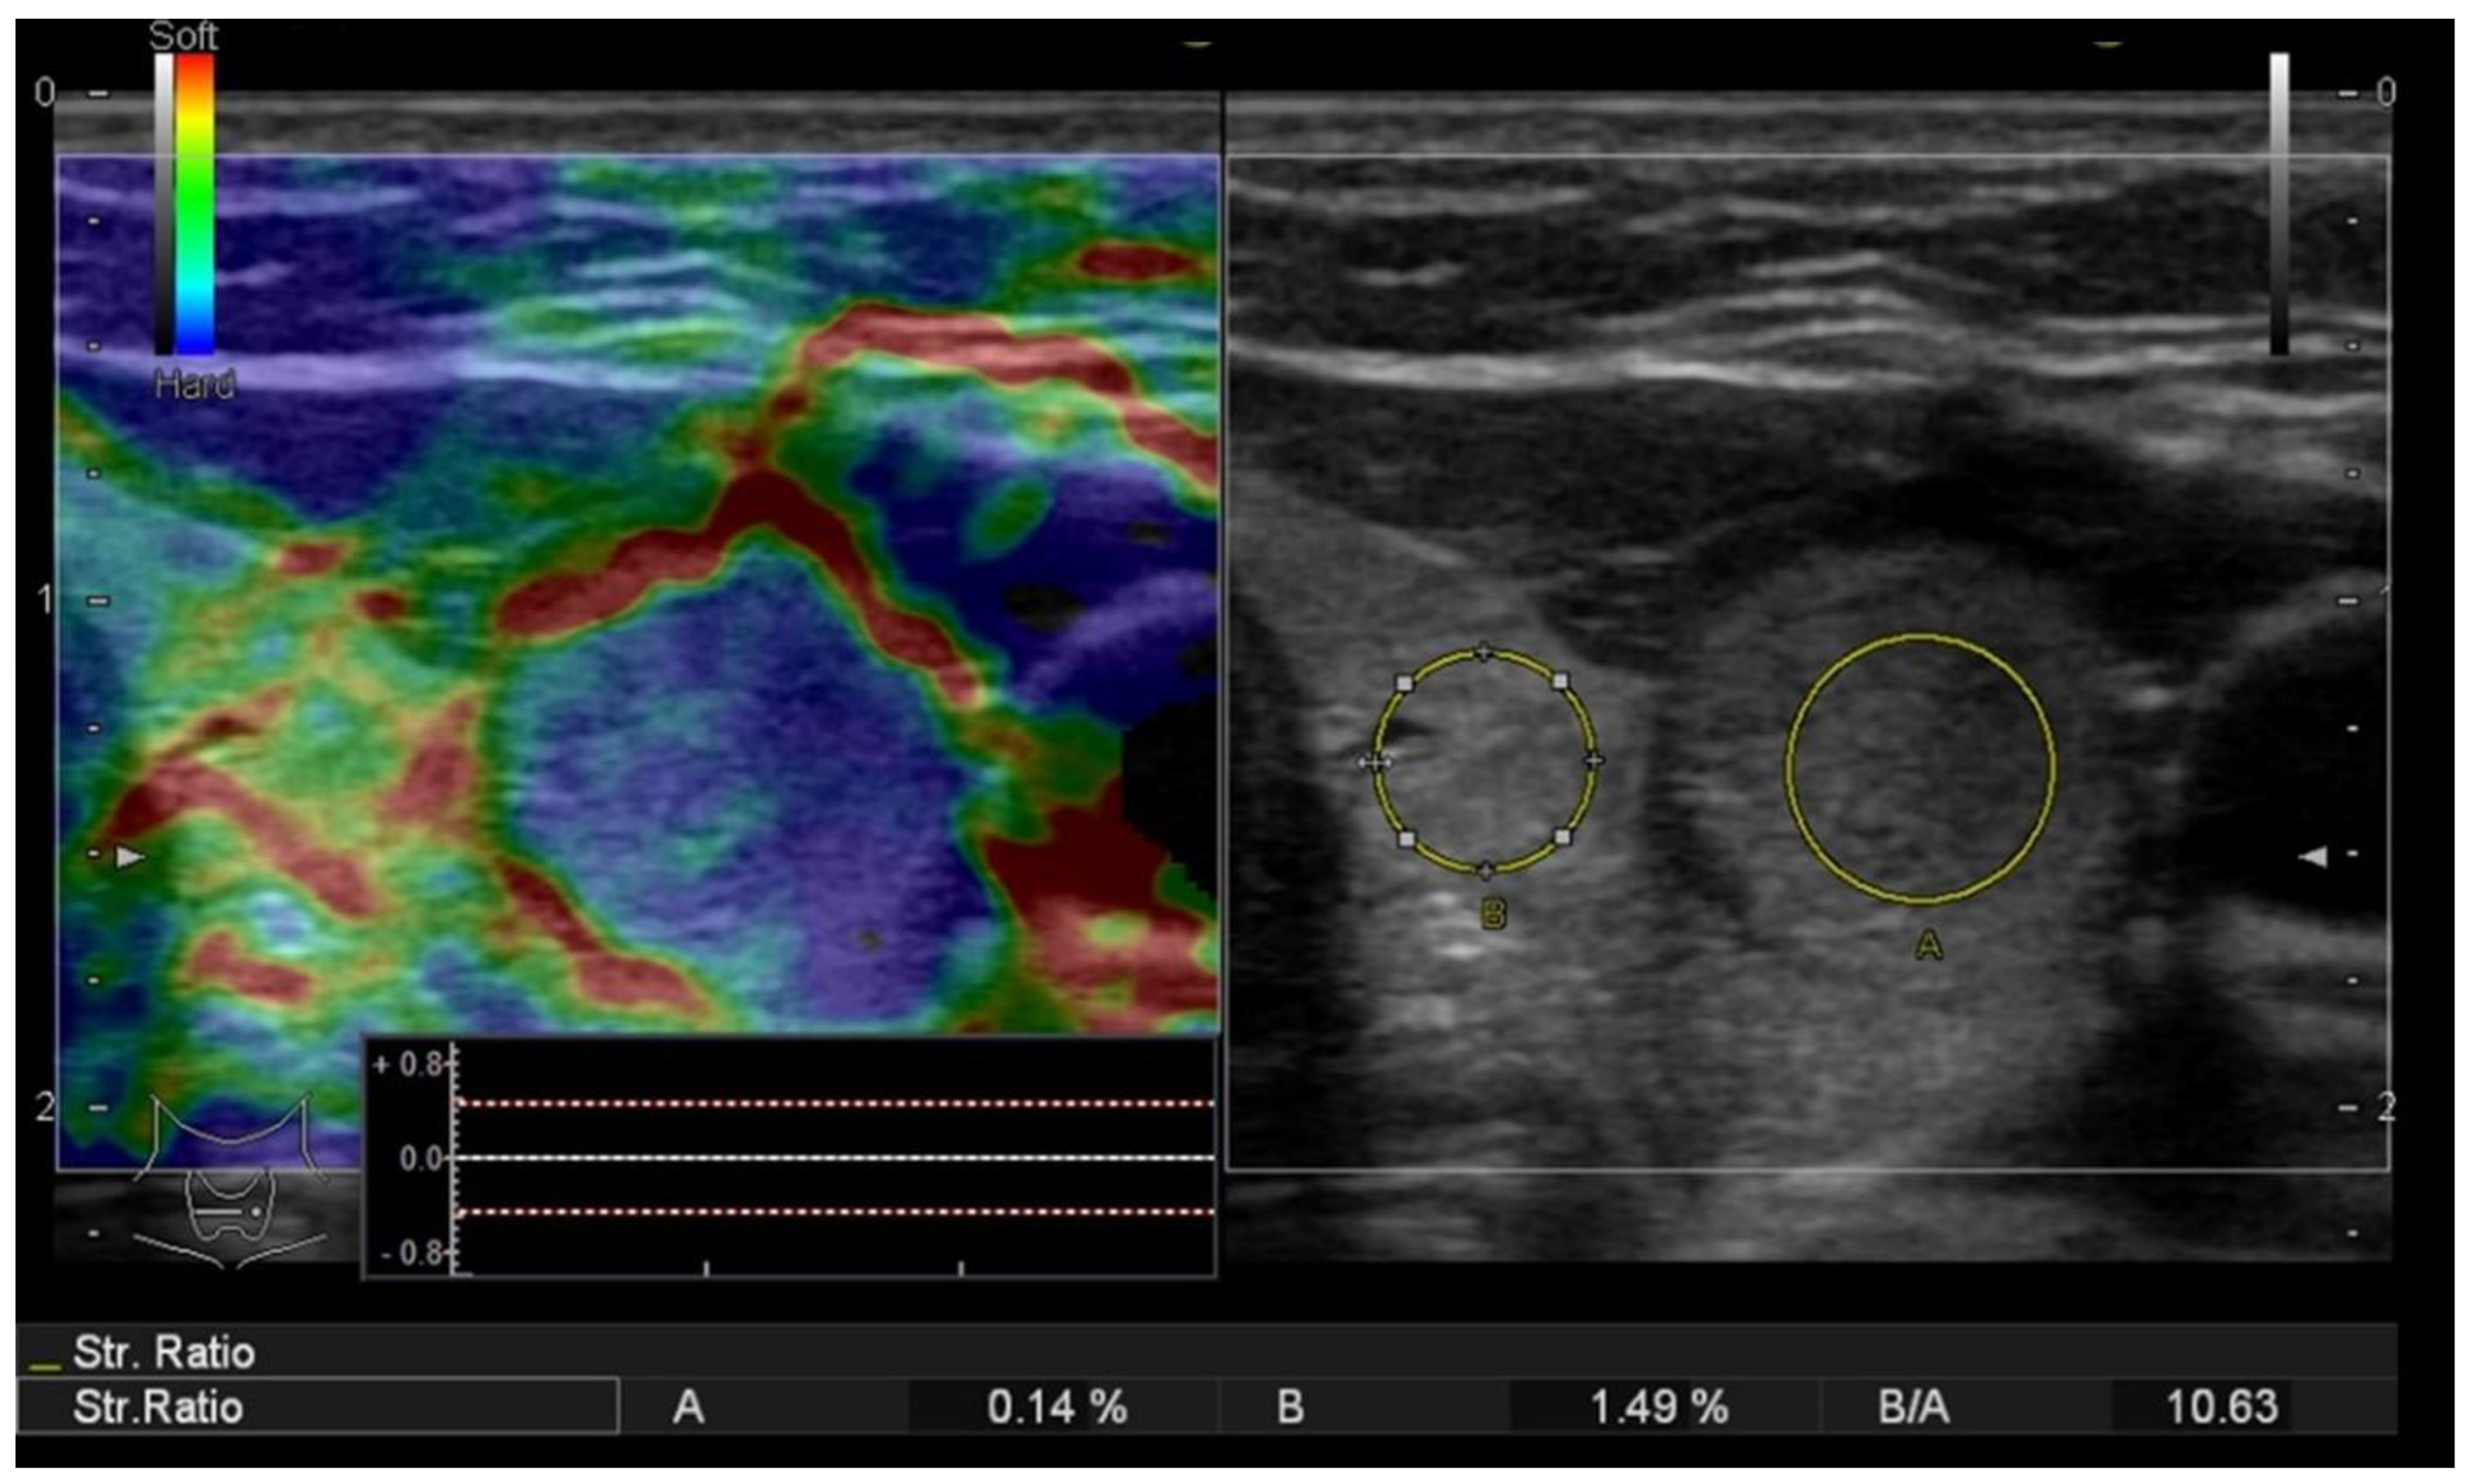

Additionally, an objective, semiquantitative evaluation providing a numeric value was also performed: the strain ratio, which shows the ratio between two ROIs that are located at similar depths, is called the parenchyma-to-nodule ratio, as exemplified in Figure 2. Longitudinal sections are preferred in order to obtain an image displaying enough surrounding healthy thyroid tissue []; in order to obtain longitudinal views, the probe is held parallel to the trachea to include the maximum length of the nodule in focus. In cases with associated autoimmune disease, when the elasticity of the surrounding parenchyma might be increased [], the semiquantitative ratio was not considered in the final analysis.

Figure 2.

Strain elastography (left) evaluation displaying a colormap overlaid on the greyscale image, Asteria score 4 (completely stiff/color blue); the nodule-to-parenchyma strain ratio (region of interest A covering the nodule and region of interest B in the healthy, adjacent thyroid parenchyma) displaying an increased value = 10.63 and the conventional ultrasound image (right) of a solid thyroid nodule.